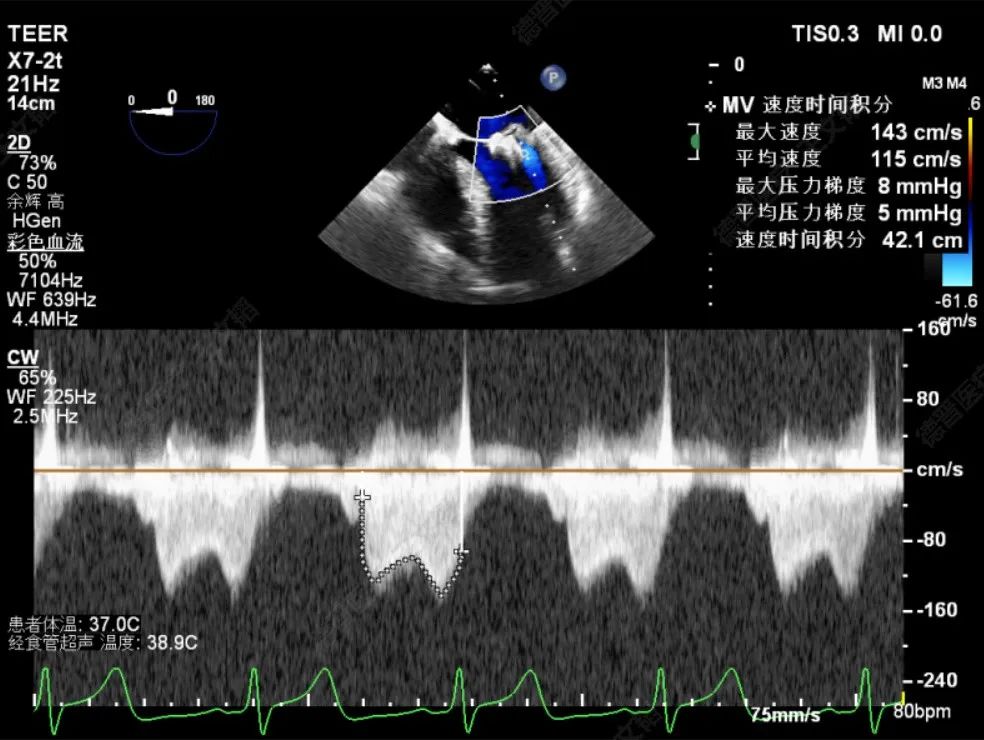

由于该患者情况特殊,潘宏伟教授、何晋教授团队通过讨论决定,先于脱垂正上方置入一枚长宽(XW0612)夹,再根据残余脱垂的情况决定是否置入第二枚夹子。术中团队利用DragonFly™刻度化旋钮及三段式可调节管身的设计,灵活调整二尖瓣夹系统,配合超声老师傅庆华教授的专业引导,成功将二尖瓣安全的打弯至二尖瓣瓣上。最后于2偏1区及2偏3区分别置入了两枚长宽(XW0612)夹。夹闭后反流由术前重度降低为Trace,跨瓣压差4mmHg,左房压由术前61mmHg降至术后27mmHg,肺静脉逆流几乎消失,效果立竿见影。

TMPG:4mmHg

术前潘宏伟教授、何晋教授团队讨论决定,先于2偏1区置入一枚长宽(XW0612)夹解决最大的一处脱垂,再依次向内侧补夹子。术中房间隔穿刺高度:4.4cm,于2偏1区植入一枚长宽(XW0612)夹,夹闭后L侧无残余脱垂。再于M侧2区Side by side植入一枚长宽(XW0612)夹,夹闭后第一枚夹子较前稳定,M侧有残余脱垂。最后于M侧2偏3区植入一枚长窄(XN0412)夹,夹闭后残余功能性反流Trace,压差5mmHg,术毕,反流即刻由术前重度降低为Trace,左房压由术前45mmHg降至术后22mmHg,肺静脉逆流几乎消失,患者明显获益。

TMPG:5mmHg